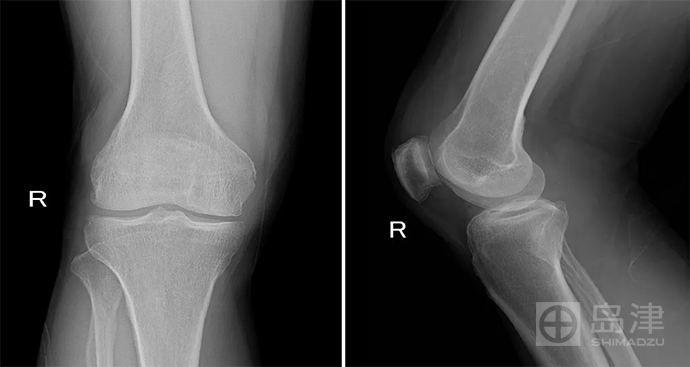

病例二 :骨折征象显示

男性 ,89岁 ,摔伤。 患者偏瘫,失语。

右侧髌骨正侧位X线未见骨折直接征象。软组织肿胀亦不明显。

放射科医师查体:髌骨区见抗拒性反应。

DTS: 右侧髌骨骨折。

隐匿性骨折 DR无法发现

右髌骨隐匿性骨折

DTS可发现平片无法发现的骨折

图像来源:西安市第九医院